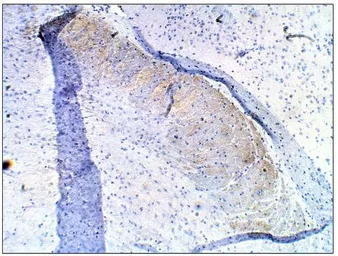

IHC-P analysis of mouse brain tissue using GTX14622 PDE10A antibody.

Dilution : 1:100